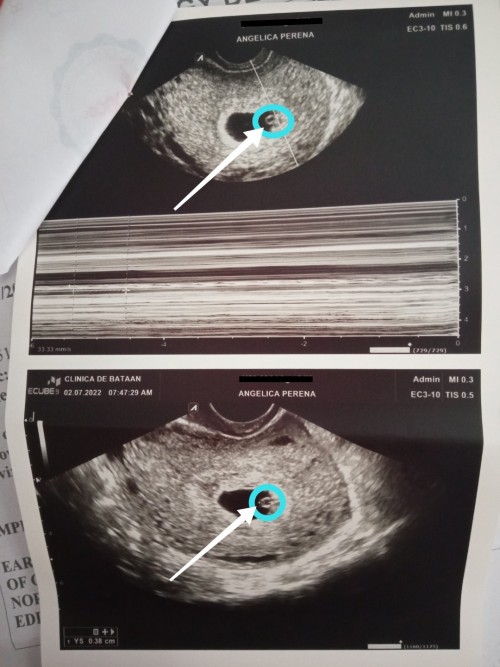

6weeks and 4days po.. mag papaultrasound lang sana ako kaya lang dipa sya makita kaya ginamitan ako ng transv..

6weeks 3days nakita na baby nmin s scan with heartbeat. pero iba iba case po minsan my late po. pray k lng mommy.

6 weeks and 1 day may HB na nakita sakin, depende po kase sa pagbubuntis, yung iba 8 weeks pa makikita talaga

First Trans-V ko kita na po agad 6weeks 1day π with heart beat π₯° (now i'm 22 weeks preg.) π